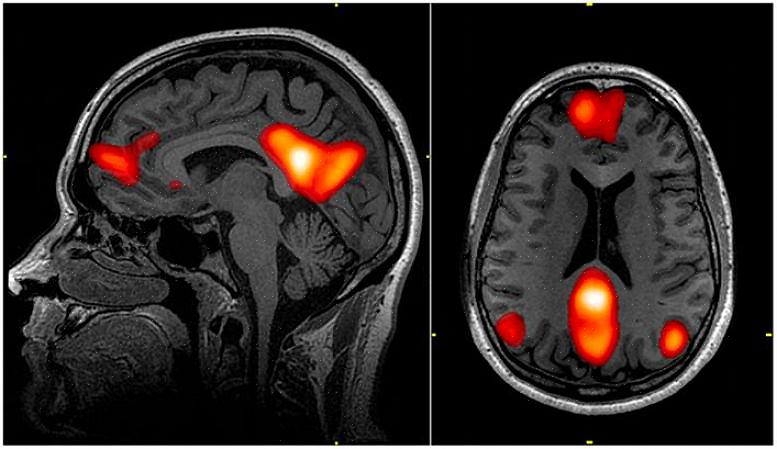

רשת מצב ברירת המחדל מורכבת משלושה אזורי מוח קונקרטיים: קליפת המוח הקדם-מצחית המדיאלית, האונה הפריאטלית התחתונה האחורית והאונות הטמפורליות המדיאליות. ד"ר מרקוס רייכל קרא למעגל שמפעיל במבנים אלה רשת מצב ברירת המחדל. עם זאת, ב-1997, כשפרסם את הנתונים שלו, החליטו בתקשורת לתת לו שמות מעניינים יותר. מכאן הגיעו מונחים כמו "רשת החלומות בהקיץ" או "האנרגיה האפלה של המוח".